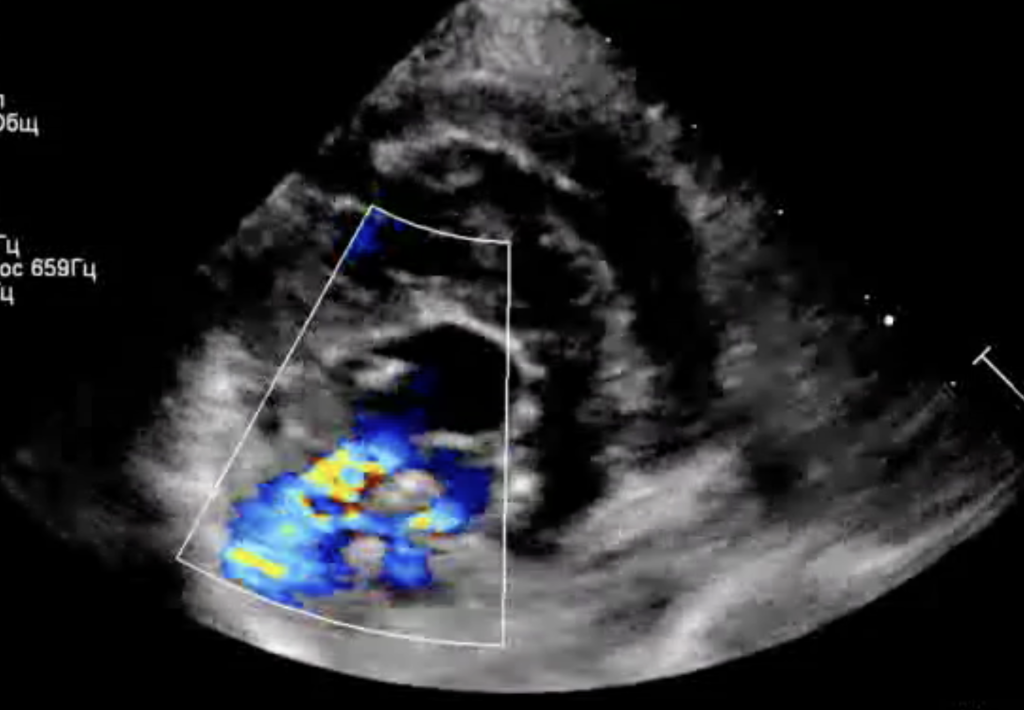

Фото 5-7. Двухмерная эхокардиография, правая парастернальная проекция, короткая ось, срез на уровне створок митрального клапана: значительное улучшение коаптации створок митрального клапана, регургитационные потоки формируются по краям от зоны их стягивания (фото 5); створки клапана стянуты край-в-край в сегменте А2, что обеспечивает основную пропускную способность клапана через зоны А1–Р1 и А3–Р3 (фото 6). Выраженное обратное ремоделирование миокарда левого желудочка (фото 7): уменьшение конечно-диастолического нормализованного размера ЛЖ до 1,3 (до операции КДРн – 1,9).

Пациент успешно стабилизировался в послеоперационном периоде.В течение первых дней наблюдалась умеренная апатия, однако аппетит был сохранен, что является положительным признаком восстановления. Эхокардиография, проведенная после операции, выявила значительное снижение степени митральной регургитации и уменьшение давления в левом предсердии с 19/13 мм рт. ст. до 11/4 мм рт. ст., что свидетельствует об успешной коррекции дефекта клапана и об эффективности проведенного хирургического вмешательства2 (фото 5-7).